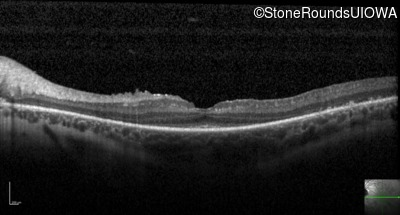

Optical Coherence Tomography - Right - 20/40 -2

Exemplar / OCT Stack